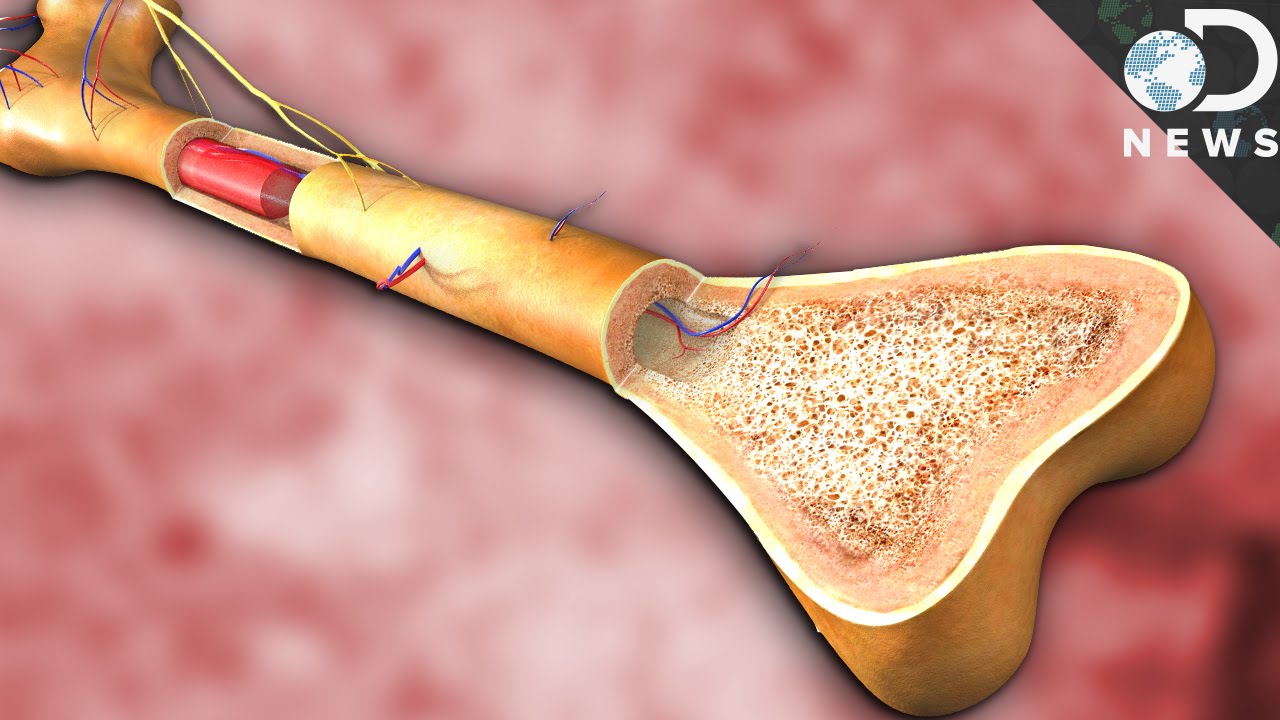

Изучение костного мозга: анатомия и функции